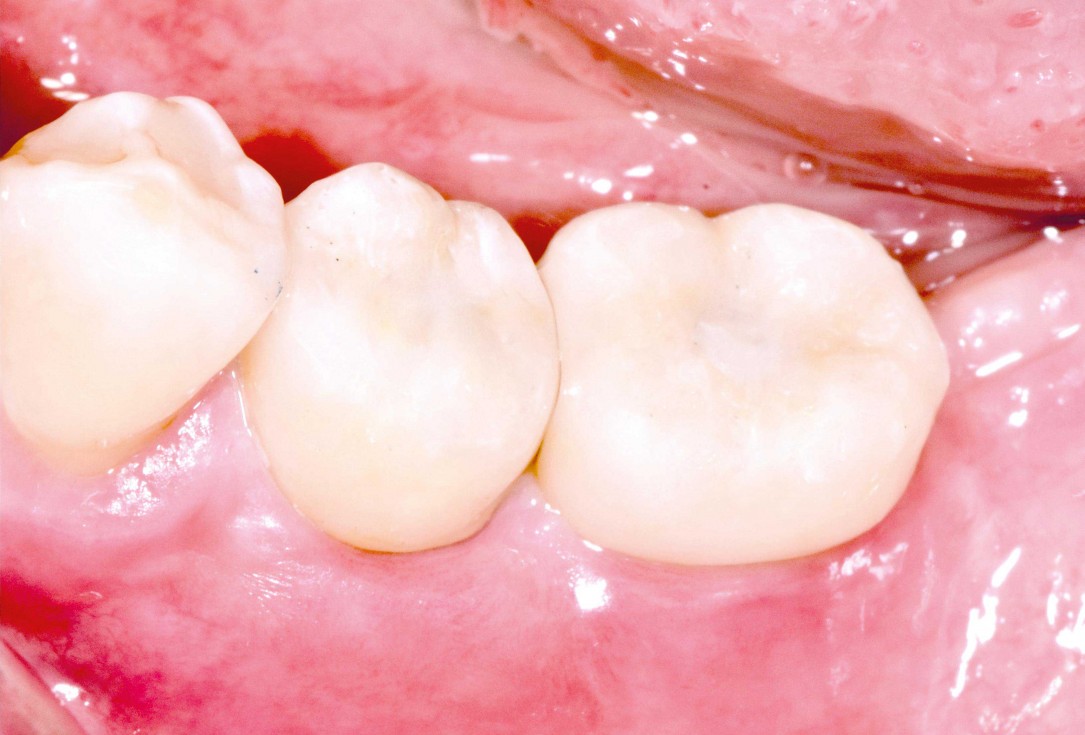

Initial clinical situation with gum recession and labial bone loss eight weeks following tooth extraction